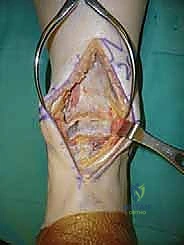

2. الشق الجراحي والنهج الأمامي (Incision & Anterior Approach)

يقوم الدكتور هطيف بعمل شق طولي دقيق في الجزء الأمامي من الكاحل، طوله حوالي 10-15 سم. يتم تشريح الأنسجة بعناية فائقة للوصول إلى المفصل.

* الحماية العصبية الوعائية: هذه هي الخطوة الأكثر حرجاً. يتم تحديد الحزمة الوعائية العصبية (الشريان الظنبوبي الأمامي والعصب الشظوي العميق) وسحبها برفق شديد لحمايتها من أي ضرر جراحي.

3. إزالة النتوءات العظمية وتحضير المفصل (Debridement)

بمجرد كشف المفصل، يقوم الجراح بإزالة الغشاء الزلالي الملتهب والزوائد العظمية (Osteophytes) التي تعيق الحركة. هذه الخطوة ضرورية لاستعادة المعالم التشريحية الطبيعية قبل إجراء القطع العظمي.